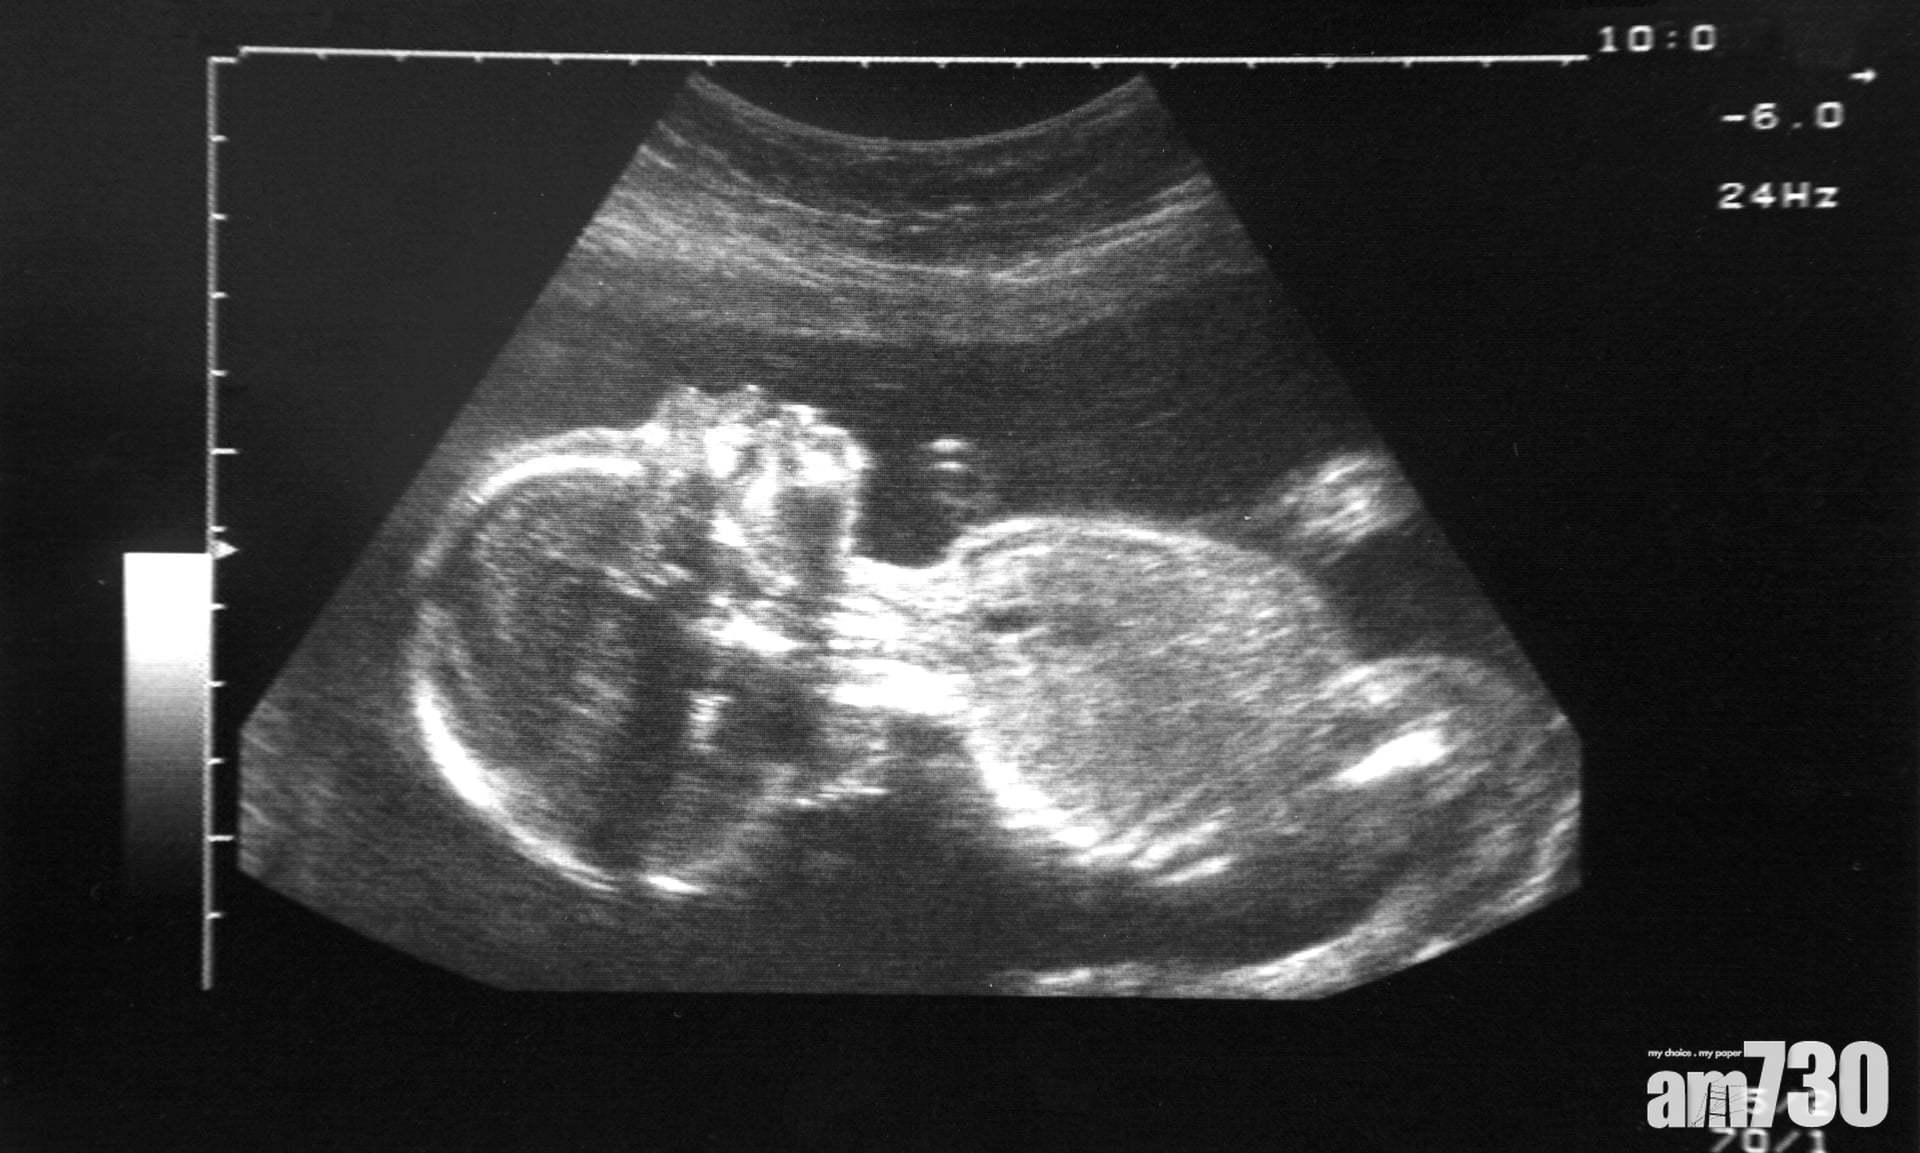

英國與比利時研究均發現,空污粒子可進入胎盤,或損害胎兒健康。

早有研究證實,空氣污染會提高孕婦流產、早產或胎兒過輕,或降低胎兒智商等的風險,污染物會對胎兒的健康造成終身損害,英國及比利時科研團隊首次發現空氣污染粒子可進入胎盤,或影響胎兒健康。